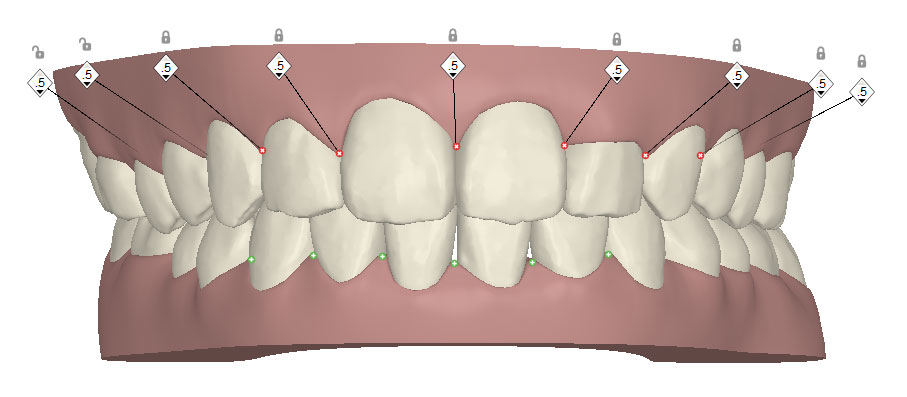

コンピューターを使って作製した透明なマウスピース型の矯正装置(アライナー)を段階的につけ替えていき、それにより歯列を矯正し、歯並びへと改善します。はじめに 治療開始から終了までのアライナーができあがってきます。マウスピース型矯正装置(インビザライン)の最大の特徴として「クリンチェック」というソフトがあります。3D のコンピュータ シュミレーション画像で、治療開始から完了までを目で見て確認することができます。

マウスピース型矯正装置(インビザライン)治療においては、クリンチェックというシミュレーションソフトを活用しております。

このクリンチェックの魅力は、治療前の現在の歯並びから治療後の歯並びを視覚化して患者様にご説明できる点にあります。

また、抜歯・非抜歯、全体矯正・部分矯正などそれぞれの治療パターンをシミュレーションすることが可能です。

| 治療前 |  |

| ライトプラン 隣接面削合なし |

| ライトプラン 隣接面削合あり |

| フルプラン 隣接面削合あり |